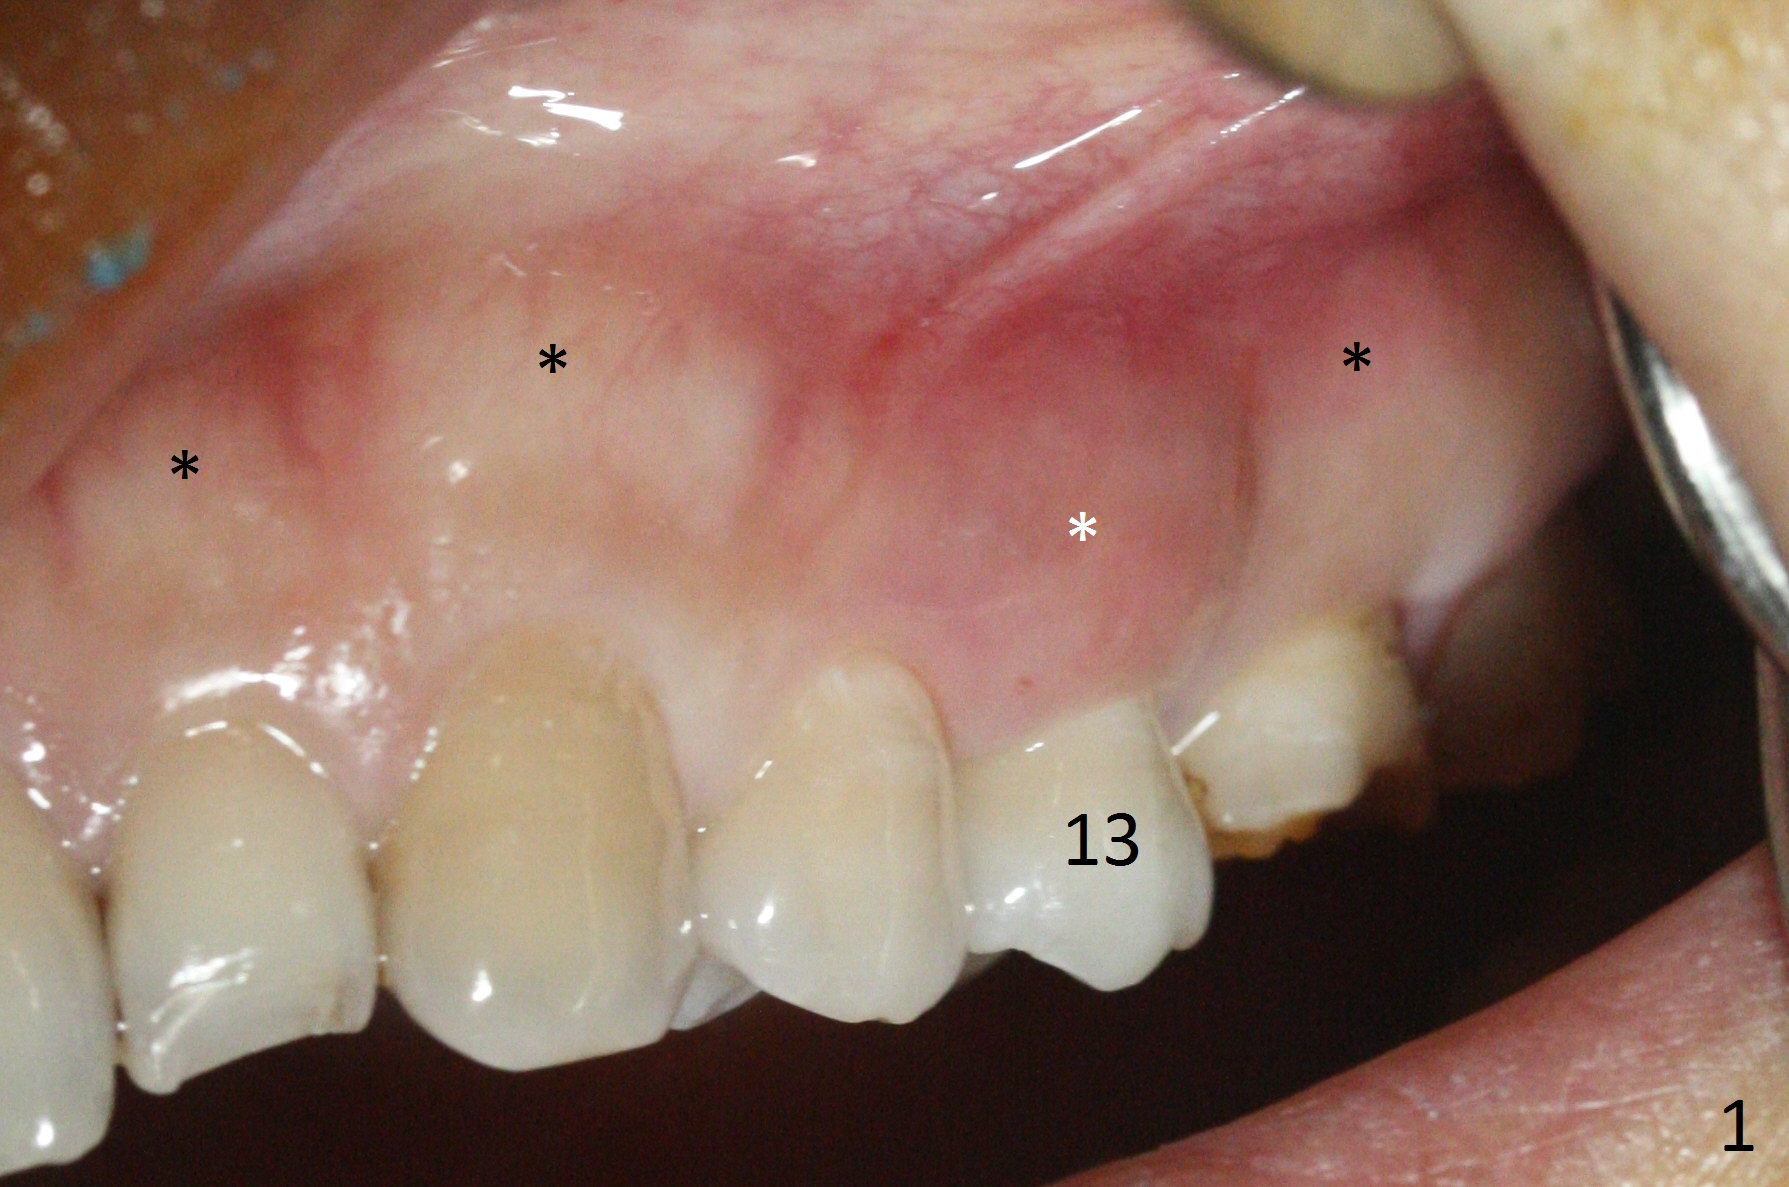

The buccal gingiva over the tooth #13 (Fig.1 white *) with crack (Fig.2 (mesial view of the extracted tooth)) is erythematous with deep buccal (B) pockets, which do not appear to extend the level of exostosis of the neighboring teeth (Fig.1 black *), i.e., coronal to the apical end of the crack with granulation tissue (Fig.2 *). Osteotomy is initiated with a 1.6 mm drill in the palatal aspect of the socket (Fig.3) so that an implant will be placed palatal (Fig.8,11) and there is enough buccal gap for bone graft (Fig.8 *). After withdrawal of 3.3 mm Magic Drill (trephine bur), the osteotomy (Fig.4 O) plug (red outline) is intentionally left in situ. When a 4x11 mm dummy implant is placed (Fig.5 (green outline), 6), the plug is compressed (Fig.5). With placement of a definitive implant (4.5x13 mm, Fig.7 (green), 9), the plug as well as the sinus floor (Fig.4 SF) is lifted (Fig.7 red curved line), 9 (arrowheads)). In brief the autogenous bone is used for sinus lift. There is no intra- or post-op nasal hemorrhage. With a small piece of gauze (Fig.8 G) in the implant well, allograft is placed in the buccal (mainly) and palatal gaps until the level of the implant plateau. Then a 4.5x4(3) mm abutment is placed (Fig.9-10 A). Next another piece of gauze is placed in the space corresponding to the abutment cuff (Fig.11 G) for fabrication of an immediate provisional (Fig.12 P). More bone graft is placed in the soft tissue zone (dual zone technique) after gauze removal and before provisional seating. With dual zone bone graft technique and provisional support, the soft tissue atrophy should be expected to be minimal (Fig.12 *). The zone of exostosis (more coronal) should be much less, since the bone density in the zone is high.